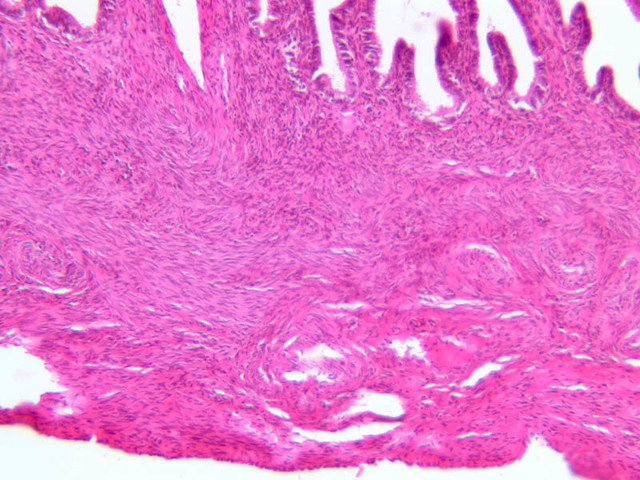

Uterine Cervix

The endometrium of the cervical canal does not slough during the menstrual phase. The glands in this region are relatively large and extensively branched. They are lined by a tall simple columnar epithelium very active in the secretion of mucus. Occasionally these glands become blocked forming Nabothian cysts. The transition of the epithelium of the cervix to that of the vagina is abrupt and is in the region of the external os. At this point, the cervical simple columnar is replaced by the vaginal stratified squamous epithelium (slide B-98 [2.5x-labeled, 10x, 20x, 40x] [2.5x, 10x, 20x, 40x]). This is an area which is commonly inflamed as well as a primary location of cervical cancer.